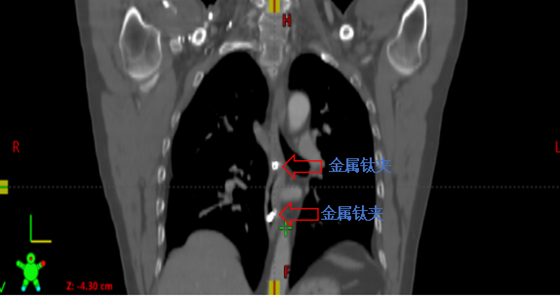

金属钛夹标记病变部位

接诊后,肿瘤科钟美佐主任同李军烽副主任医师结合患者既往病史和实际情况决定对病变部位实施放射治疗。考虑到患者食管病变较早,CT无法清晰显示病变部位及范围,患者曾经又接受过上段食管放射治疗,为进一步减少照射范围,准确定位肿瘤位置,肿瘤科联合消化内科,通过消化内镜在原位癌处附近植入金属钛夹标记物后再行增强CT,根据钛夹位置对病灶实施精准定位,尽可能的减少不必要的照射,降低患者放疗副作用的发生。目前高大哥已结束放射治疗,不适症状得到明显缓解。